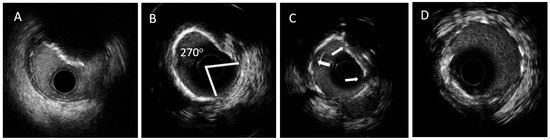

| Calcium appearance | Bright hyperechoic signal (echodense) with posterior ‘’acoustic shadow’’ | Low signal intensity areas with well defined borders |

| Criteria of calcium severity and risk of stent underexpansion indicating the need for lesion modification | Superficial calcium angle of >270° (longer than 5 mm) 360° angle of superficial calcium Calcified nodule Vessel diameter ≤ 3.5 mm | Calcium max angle > 180° Calcium max thickness > 0.5 mm Calcium length > 5 mm |